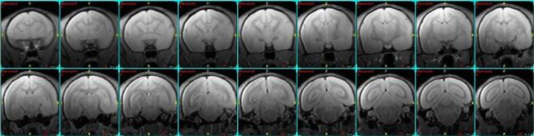

- アカゲサルの resting state fMRI

Oxytocin 投与前後の functional connectivity(oculomotor network の cross correlation)

アカゲザル(n=2)のグループ解析 - ラットのresting state fMRI